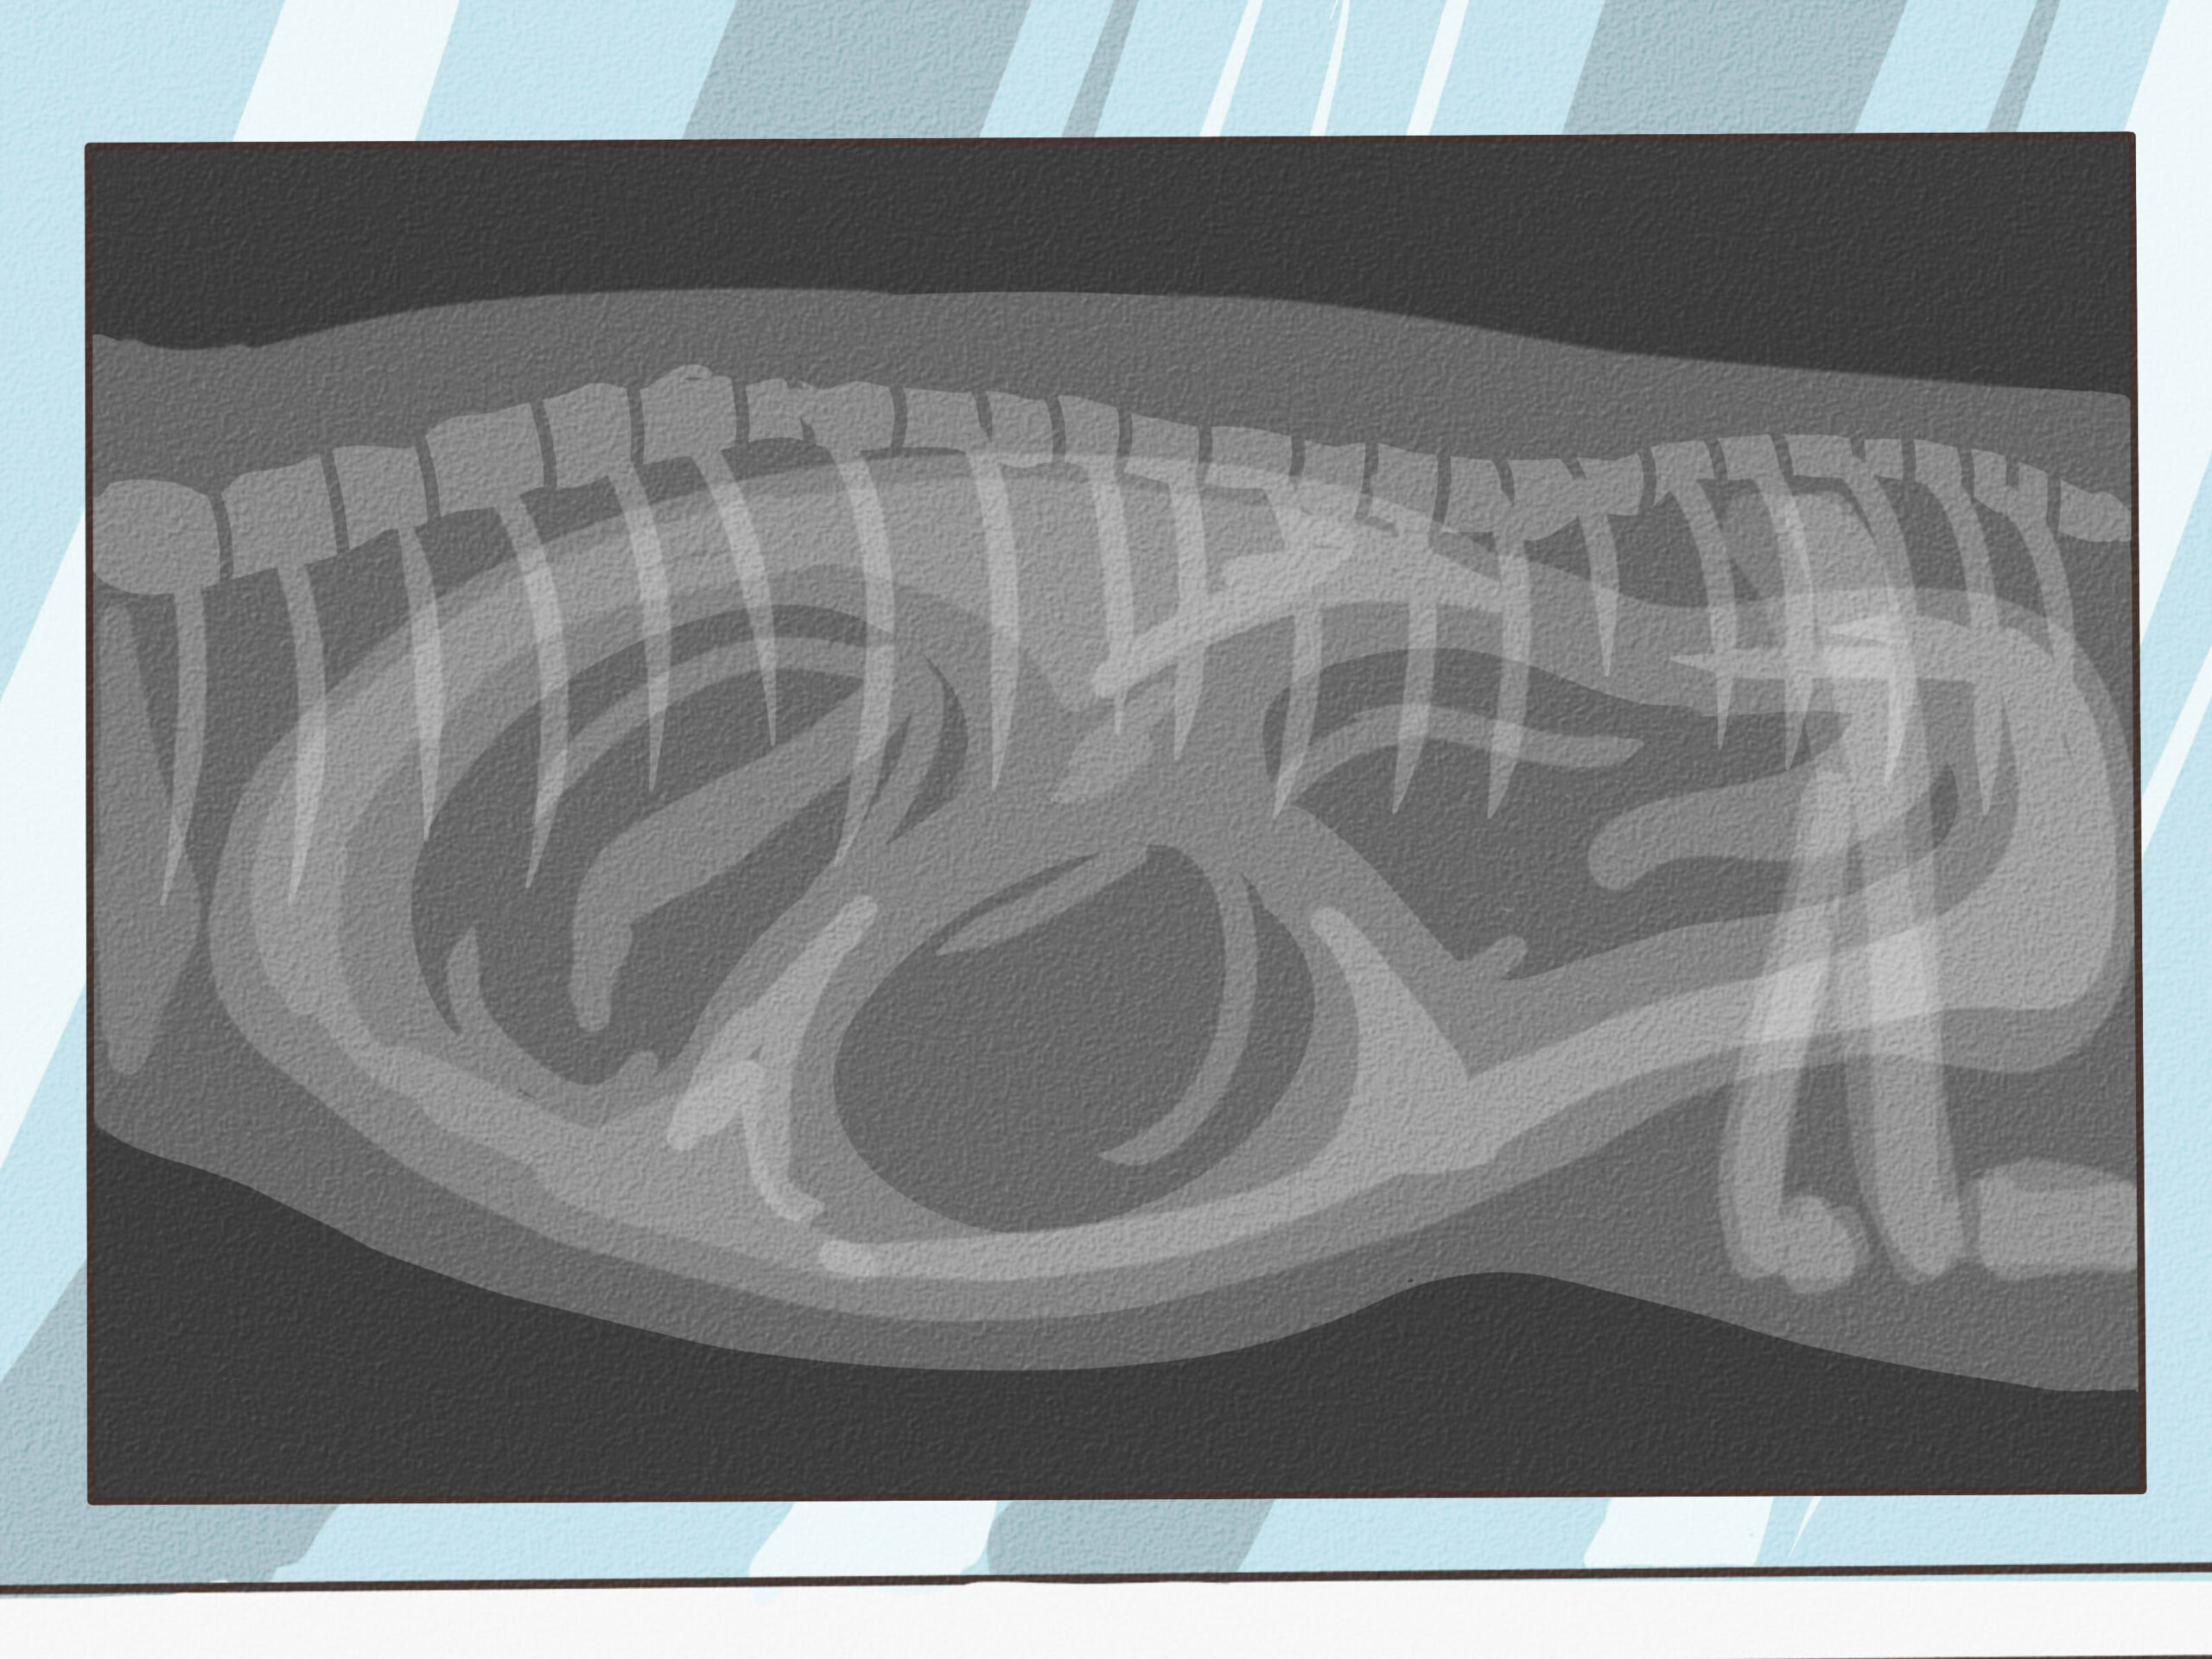

X-ray

{“smallUrl”:”https://www.wikihow.com/images/thumb/0/0e/Tell-if-a-Dog-Is-Pregnant-Step-11-Version-5.jpg/v4-460px-Tell-if-a-Dog-Is-Pregnant-Step-11-Version-5.jpg”,”bigUrl”:”/images/thumb/0/0e/Tell-if-a-Dog-Is-Pregnant-Step-11-Version-5.jpg/v4-728px-Tell-if-a-Dog-Is-Pregnant-Step-11-Version-5.jpg”,”smallWidth”:460,”smallHeight”:345,”bigWidth”:728,”bigHeight”:546,”licensing”:”<div class=”mw-parser-output”><p>u00a9 2023 wikiHow, Inc. All rights reserved. wikiHow, Inc. is the copyright holder of this image under U.S. and international copyright laws. This image is <b>not</b> licensed under the Creative Commons license applied to text content and some other images posted to the wikiHow website. This image may not be used by other entities without the express written consent of wikiHow, Inc.<br>n</p><p><br />n</p></div>”}An X-ray of your dog’s stomach can help veterinarians count the number of puppies.[14]

X

Licensed VeterinarianExpert Interview. 8 October 2021.

With ultrasounds being the main test for dog pregnancies these days, an X-ray is only used in cases where the exact number of puppies needs to be known or there are suspected complications.- If you have a smaller dog, the veterinarian may take an X-ray to calculate the size of the puppies to determine whether a natural birth or c-section is the safest option.